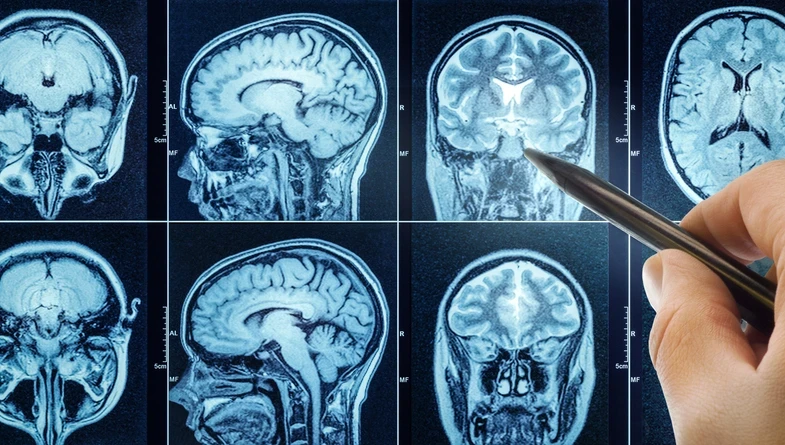

Beyin, binlerce kıvrım ve yoldan oluşan karmaşık yapısıyla tıbbın en zorlu çalışma alanlarından biri olmayı sürdürüyor.

Bu kapsamda nöronavigasyon teknolojisi cerraha tümöre ulaşması için en kısa ve güvenli rotayı belirleyen dijital bir yol haritası sunarken; fonksiyonel MR ve traktografi yöntemleri beynin konuşma, hareket ve görme gibi hayati merkezlerini haritalandırarak bu kritik bölgelerin korunmasına yardımcı oluyor.